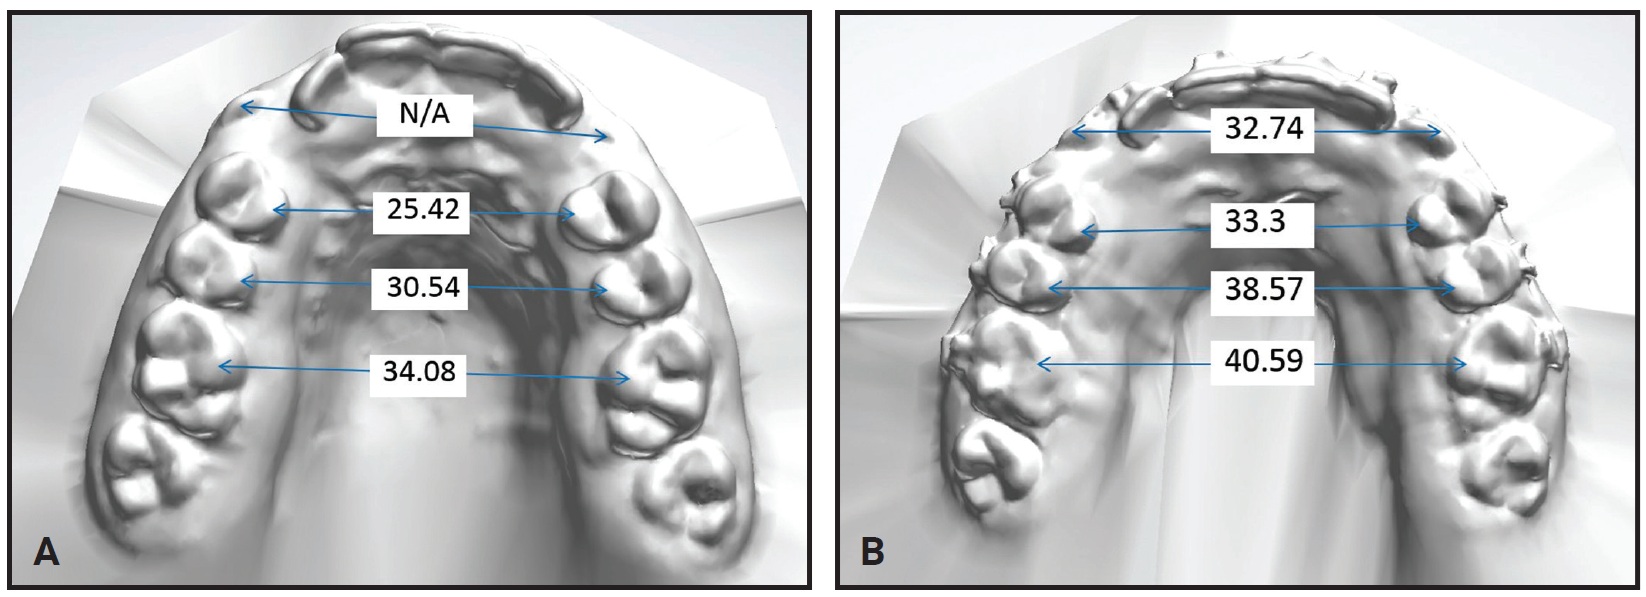

After intermolar expansion of 3.87mm had been obtained (Fig. 3, Table 1), flowable composite was placed in the expansion screw housing to stabilize the appliance. A maxillary impression was then obtained and digitized to evaluate the molar angulation changes (Fig. 4). Bony separation suggesting mild sutural disruption was indicated by radiolucency on the occlusal radiograph (Fig. 5).

Fig. 3 Case 1. Maxillary dental arch-width measurements (mm) before (A) and after (B) expansion.

Fig. 8 Case 2. Maxillary dental arch-width measurements (mm) before (A) and after (B) expansion.